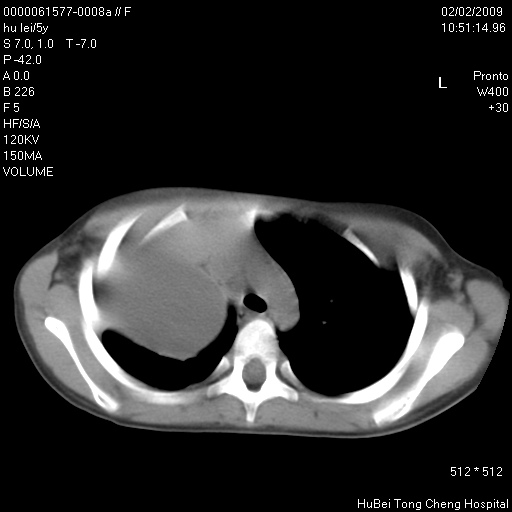

标题: PED1732:M5Y,右肺囊性占位!

患者:男,5。无明显不适,拍胸片考虑右肺囊肿。

行ct扫描,图象如下: